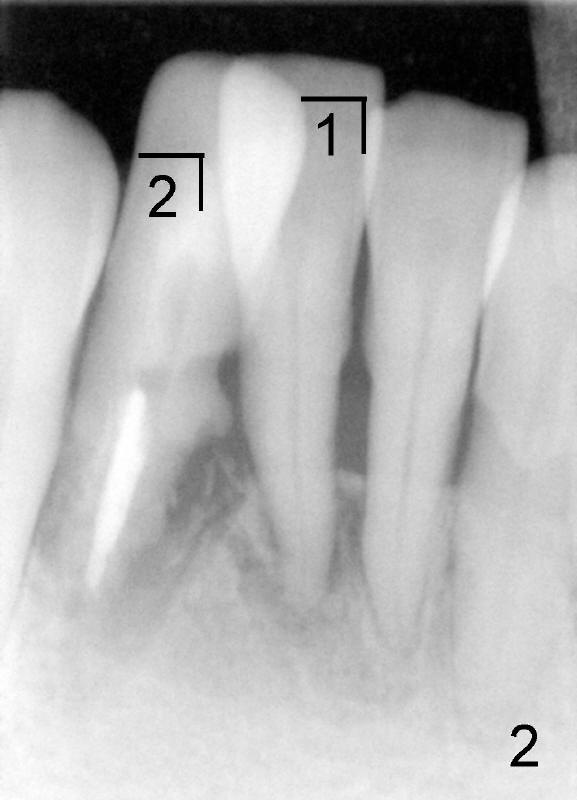

A 60-year-old lady wants to remove 2 mobile lower right incisors (Fig.1,2; with infection at the lateral (>)). Immediate 1-piece implants are placed (Fig.3,4): 3x17 mm at the central, 3.5x17 mm at the lateral. Insertion torque is > 60 Ncm for the implants. No bone graft is placed. After prep (Fig.5), two separate provisionals are fabricated (Fig.6). The one at the lateral incisor looks bulky at the cervix, because of the oversized implant for the site (over-engineering). Use of smaller implant (3.0 (instead of 3.5), 2.5 (instead of 3.0) or 2.0 mm) may solve the problem. Seven days postop, the infection resolves (Fig.7 >) with normal-looking papilla (*).